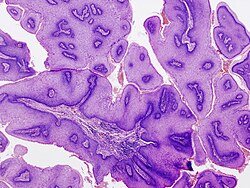

| Condyloma acuminatum | koilocytes | parakeratosis, long folded rete ridges (papillomatosis) - pseudopapillary look | genital lesion | none (p16+) | fibroepithelial polyp | caused by HPV | |